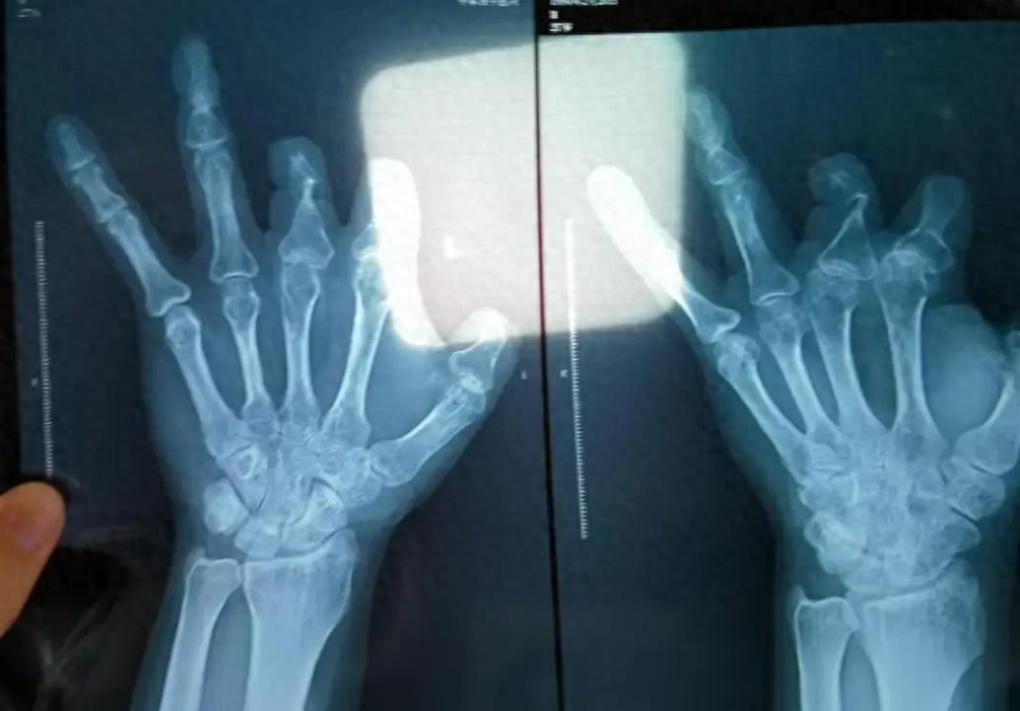

这事儿听得我后脊背发凉,医生为了拿20%的回扣,骗病人花10万块钱买昂贵的吻合器,结果吻合器压根没使用,转手就被医生扔进了垃圾桶!而警方深入调查,更是大吃一惊,被坑的不是一个人,而是整整94人!网友:简直刷新了做人的底线。 想象一下,当你拿着一张刚拍出来的X光片,在那本该显示着精密金属器械的骨骼间隙里,看到的却是一片死寂的黑白——没有金属的反光,没有高科技的痕迹,什么都没有。 这不是魔术,这是发生在河南的一场真实梦魇。彭先生当时就在那个令人窒息的诊室里,盯着那张底片发愣。按照账单,他的身体里此刻应该躺着6枚单价1.68万元的“微血管吻合装置”,总价值超过10万。 但现实是,这10万块钱买来的“救命零件”,根本没进他的血管,而是转身就被扔进了郑州大学第一附属医院的手术室垃圾桶。 这不是个例,而是一条因为贪婪而精密运转的流水线。 就在去年,也就是2025年,随着法院的终审锤音落下,急诊外科那位曾经风光无限的副主任医师王福建,终于领到了他迟来的“价码”:有期徒刑12年。 但在我们翻开这40万罚金和12年刑期的判决书之前,你得先看看这个数据背后的荒诞:94个人。 从断了手指的木工,到只有1岁大的幼童,在这位名医眼里,他们不再是需要救治的肉体,而是一台台等待刷卡的“提成终端机”。 仅仅为了拿到代理商承诺的那20%回扣,他在四年时间里,疯狂虚构了205万元的医疗账单,把105万元的黑钱揣进了自己的口袋。 最讽刺的地方在于,王福建并不是那种手艺潮烂的庸医。恰恰相反,在圈内人看来,他的手工缝合技术相当精湛。 他心里比谁都清楚,对于某些细小的血管,极其昂贵的机械吻合器其实并不好用,老老实实的一针一线手工缝合,效果反而更好。 但他面临着一个恶魔般的博弈:用最好的技术救人,只能拿死工资。把昂贵的器械扔进垃圾桶,再用手工缝合把血管接上,既能治好病,又能把那20%的回扣落袋为安。 于是,手术台变成了他的“表演舞台”。为了让这个谎言闭环,他甚至开发出了一套令人毛骨悚然的“反侦察技术”。 有些时候,为了应付术后的X光检查,他会故意把那些昂贵的金属吻合器缝在血管旁边的肌肉组织里。 你没听错,就是缝在无关紧要的肉里。这就好比修车师傅收了你换发动机的钱,却把新零件扔在后备箱里听响,车子跑得动全靠他那双巧手瞎对付。 这是一场精心设计的障眼法:一边是高超的医术在缝合血管,一边是贪婪的人性在缝合谎言。 直到2021年丑闻第一次被媒体撕开裂口时,事情的走向还一度变得非常魔幻。 你敢信吗?在那样确凿的证据面前,医院竟然还试图恢复他的执业资格。王福建甚至打起了“金蝉脱壳”的算盘,申请提前退休,试图带着那一百多万赃款安全着陆。 在那两年的博弈期里,监管系统在面对一位“技术权威”时表现出的软弱与迟钝,简直让人叹为观止。 如果不是警方在2023年底雷霆收网,这位身披白大褂的“精算师”恐怕现在正躺在某个海滩上享受他的退休生活。 虽然现在是2026年,王福建已经开始了他在铁窗下的第一年,但对于木工王海森来说,正义来得太贵了。 2018年,他在工地被电锯削掉了拇指。为了支付那张并没有使用过的“吻合器”账单,他欠下了3万多块钱的债。 对于一个靠手艺吃饭的农民工,这意味着什么?意味着在伤愈后的半年里,他不敢停工,不敢休息,像牲口一样干活,只为了偿还那笔被医生扔进垃圾桶的“冤枉钱”。 当那张空空如也的X光片最终摆在王海森面前时,他失去的不仅仅是那几万块钱。 此案最大的后遗症,从来不是那200多万的涉案金额。 它创造了一种可怕的“防御性就医”逻辑:难道以后我们做完手术,第一件事不是感谢医生,而是要立刻去拍个片子,查验一下医生有没有偷工减料? 当信任的链条断裂,修复它的成本是无限大的。 医生把吻合器扔进了垃圾桶,但在这个过程中,被一并遗弃且再也捡不回来的,是那份对“医者仁心”本能的、无条件的信任。 那张黑白的X光片,照出的不仅是消失的器械,更是人性深处最黑暗的空洞。